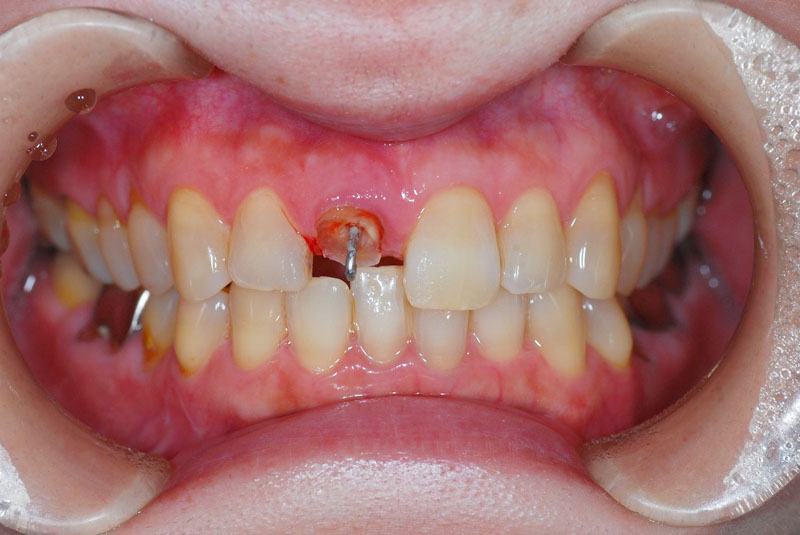

前歯のインプラント

-

術前

術後

- 患者

- 30代女性

- 主訴

- 他院で治療中の歯が折れて無くなった。

前医で前歯の治療を数か月していたが抜歯を勧められた。悩んでいたところ歯が折れてしまった。

- 治療経過

- 両側の歯を削りたくないのでインプラント治療を希望された患者さんです。前歯部インプラントの難易度はずばり審美性です。前歯なのでできる限り隣の歯と合わせる必要があります。特に1本欠損で両側が天然歯というのは難易度の高い症例です。この患者さんは決断が早く、歯槽骨まで感染が及んでいなかったため抜歯と同時のインプラント埋入を行うことで骨移植等を行うことなく治療可能でした。前歯は場合によっては審美性を確保するために歯肉移植が必要なことも多く、当院では歯肉移植を行うかどうかは患者さんと相談させていただいております。

- 治療費

- インプラント検査 3.3万円

前歯部インプラント手術 24.2万円

抜歯即時埋入加算 3.3万円

インプラント仮歯 1.5万円

アバットメント 7.7万円

ジルコニアレイヤリングクラウン 13.2万円

計 53.2万円

- 治療回数・期間

- 8回 9か月

- リスク

- 手術後の腫脹、出血、疼痛

術後感染

インプラント脱落

インプラント周囲炎

上部構造破折

歯肉退縮による審美障害

自由診療で保険が効かない